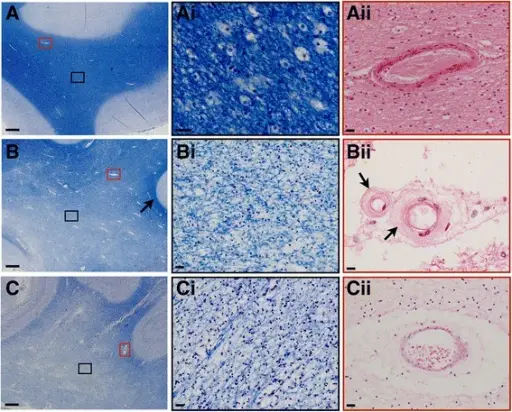

Aortic dissection is caused by shearing force allowing blood leaking through the media of the aortic wall due to an intimal tear.

Aortic dissection occurs in the high-stress zone of the proximal portion of the aorta and is accompanied by medial weakening.

- Hypertension in elderly persons, characterized by vasa vasorum hyaline arteriosclerosis

- Genetic connective tissue abnormalities in younger individuals such as Marfan syndrome or Ehlers-Danlos syndrome, characterized by weak connective tissue and cystic medial degeneration

The media sags as a result of decreased flow.

Weakness of the connective tissue in the media is a characteristic symptom of Marfan syndrome and Ehlers-Danlos syndrome (cystic medial necrosis).